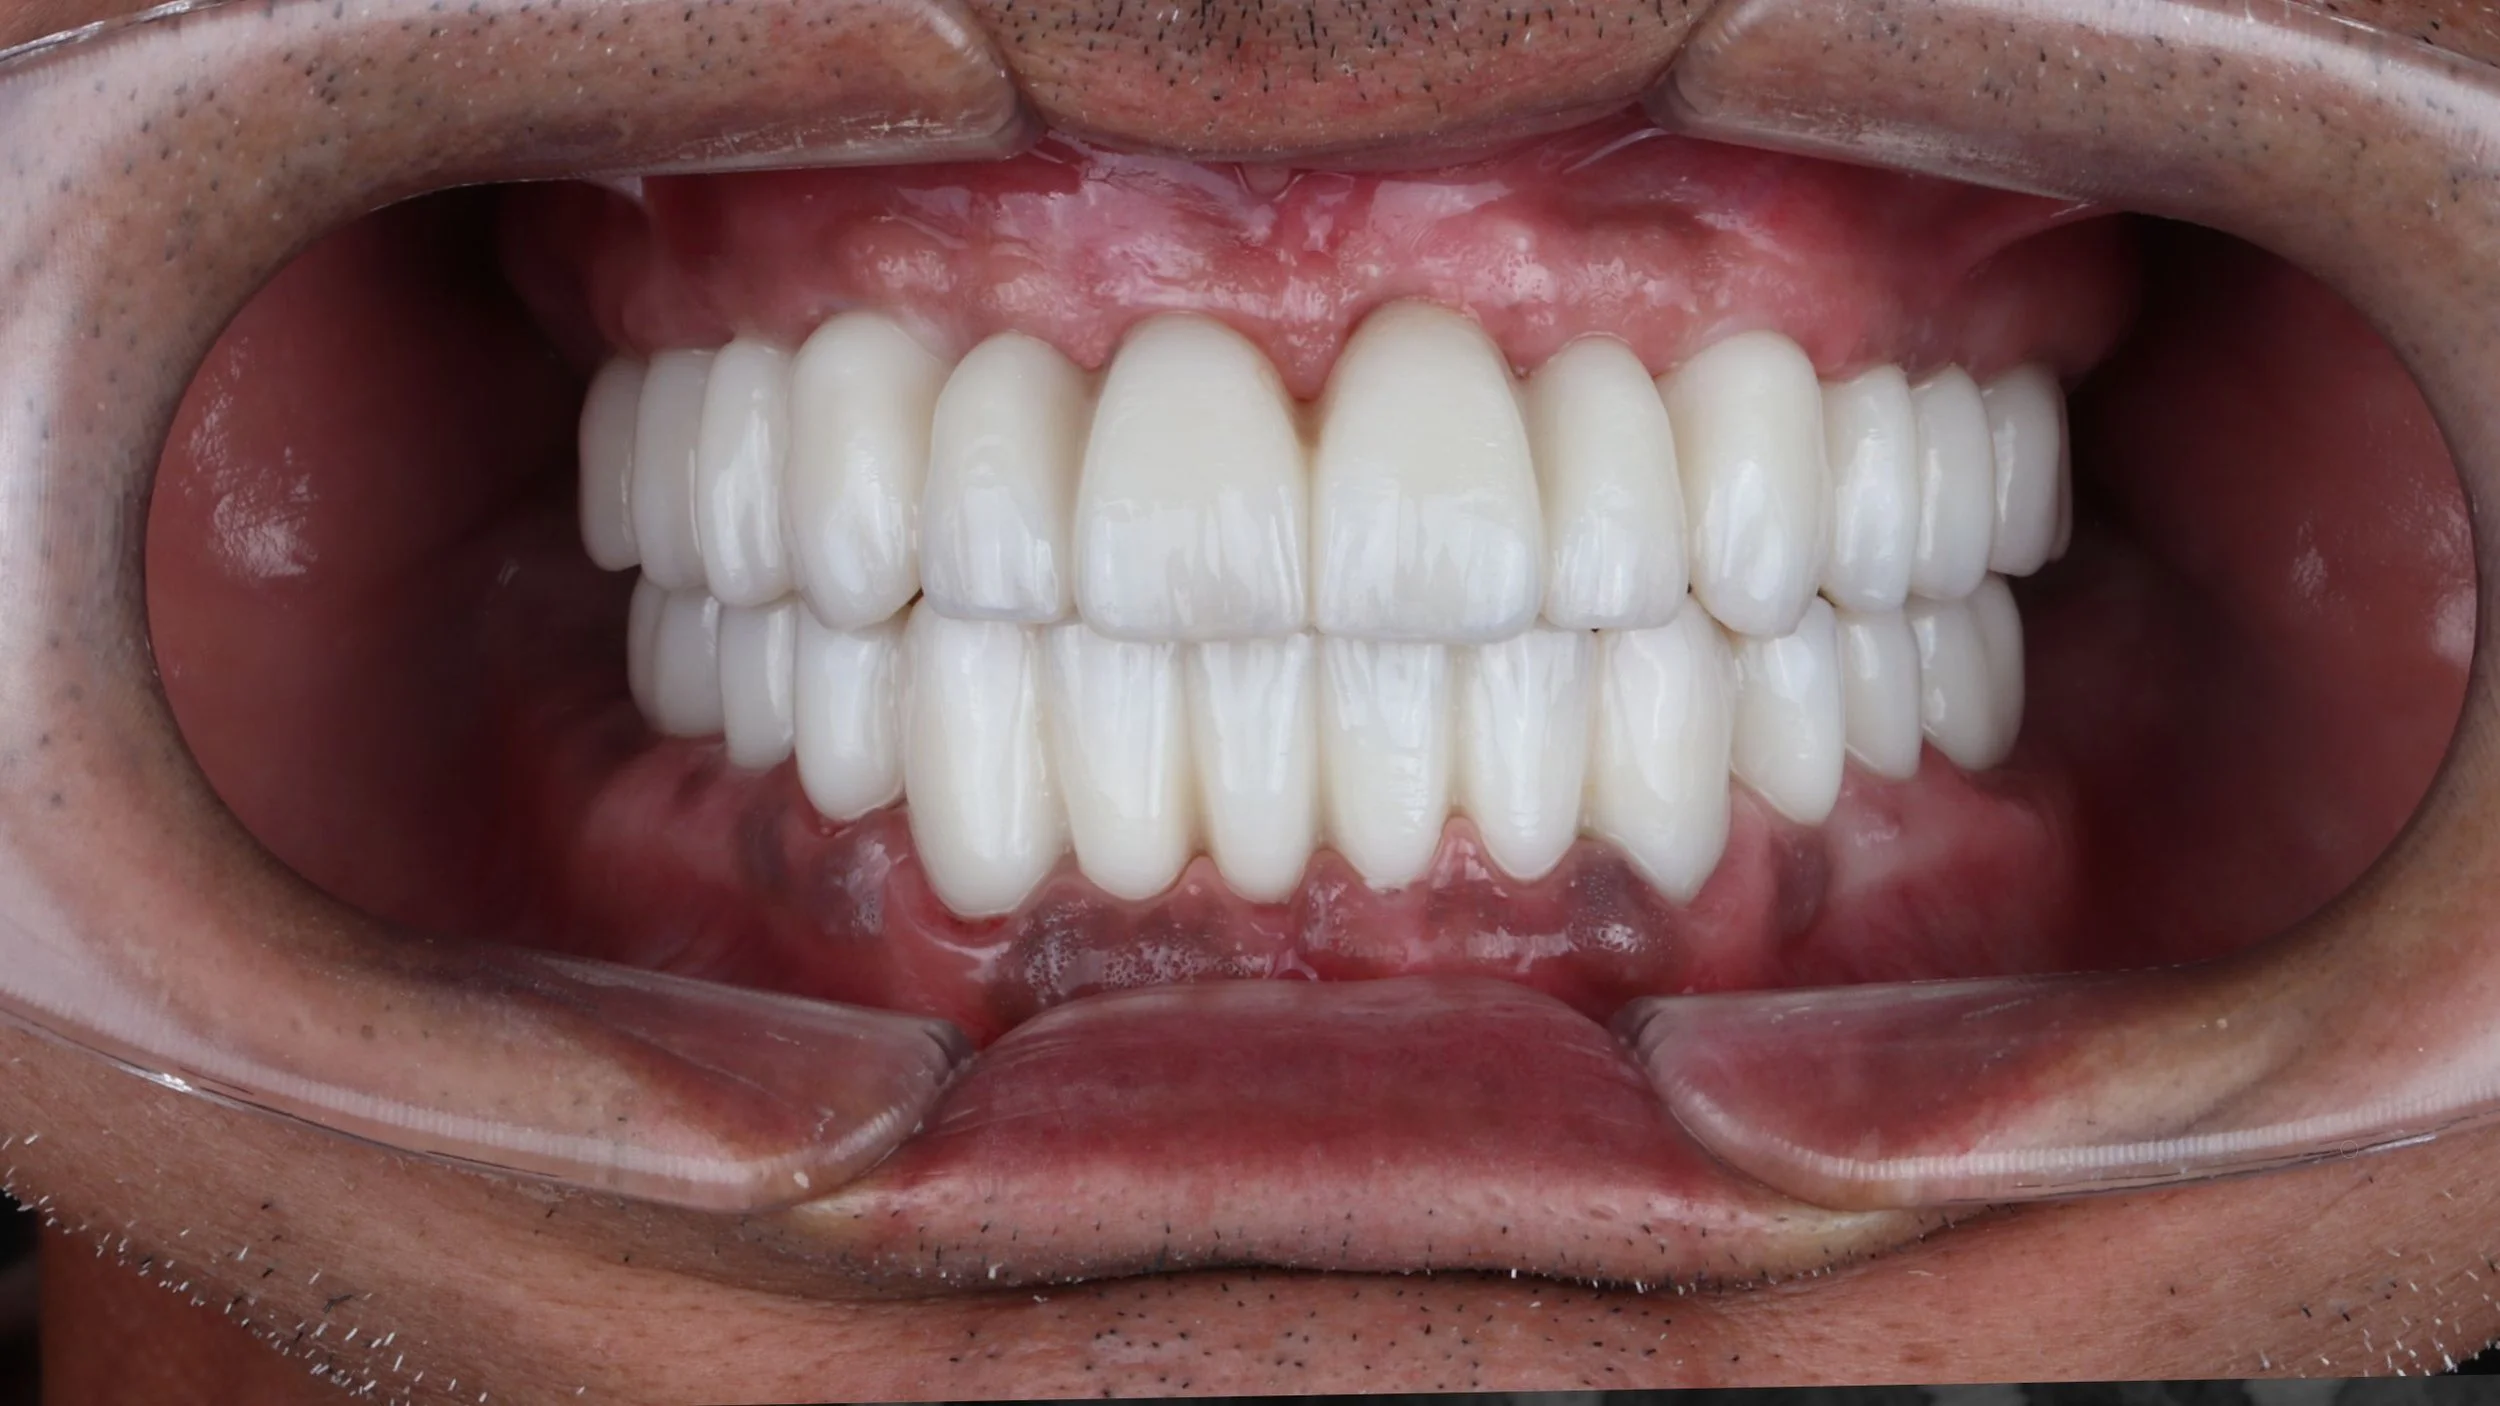

Full mouth rehabilitation can be 100% digital. From planning, to surgery, to final prosthetics.

Would you like to learn, how to do full mouth rehabilitation prosthetics without impression or photogrammetry and still achieve 100% passive fit? Just using intraoral scanner and CBCT.

2. How to make Full Arch Zirconia Prosthetics directly to the MUA abutment. Without the need of ti-base / cylinder. Allowing us to achieve stronger prosthetics, less framework fractures, better aesthetics and less cost.

This course teaches how to design and shape the dental line with immediate patient loading, making FP1, FP2, and FP3 treatments predictable without the need for Ti-base, going straight to zirconia.

PROOF OF CONCEPT AND USABILITY

• Up to 10 years of follow-up data with this protocol

• 300 completed cases (93% prosthetic success rate 2017-2024 on 148 arches)

Medical case using R2GATE guided surgery and AnyRidge implants